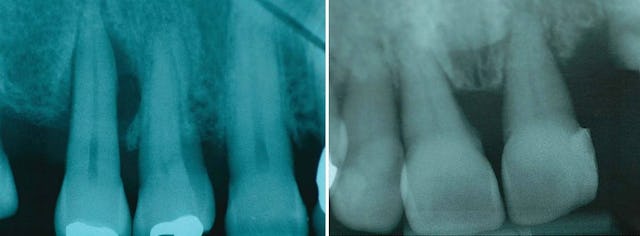

Die Folgen einer Parodontitis sind im Endstadium für den Zahn fatal und für den Patienten äusserst unangenehm.

Im Bild links sehen wir einen Zahn mit sehr tiefen parodontalen Taschen. Unter und auf dem Zahnstein befinden sich immer Bakterien, welche früher oder später zu einer massiven Entzündung des Zahnfleisches und danach zu einer Entzündung des Knochens führen, in welchem der Zahn verankert ist. Der abgebildete Zahn links hat keine gute Prognose, die Tasche ist schon zu tief und eine Extraktion (Entfernung des Zahnes) wird nötig sein, da sich der Knochen nicht regenerieren kann. Alternativ wäre eine Behandlung denkbar, weil noch keine Entzündung bis zur Wurzelspitze vorhanden ist und der Zahn noch vital ist. Diese Behandlung ist allerdings sehr aufwändig und erfordert eine sehr intensive Mundhygiene seitens des Patienten und die Prognose bleibt trotzdem noch schlecht.

Die oben bereits beschriebene Entwicklung, Bakterien (Plaque) + Zahnstein, welche zur Entzündung und zum Knochenabbau führen, werden hier auf den oberen vier Bilder nochmals verdeutlicht. Auf dem dritten Bild sehen wir deutlich den Knochenabbau in der Höhe und auf dem letzten Bild den vertikalen Einbruch. In diesem Fall sprechen wir von einer schweren Parodontitis (Entzündung des Zahnhalteapparats).